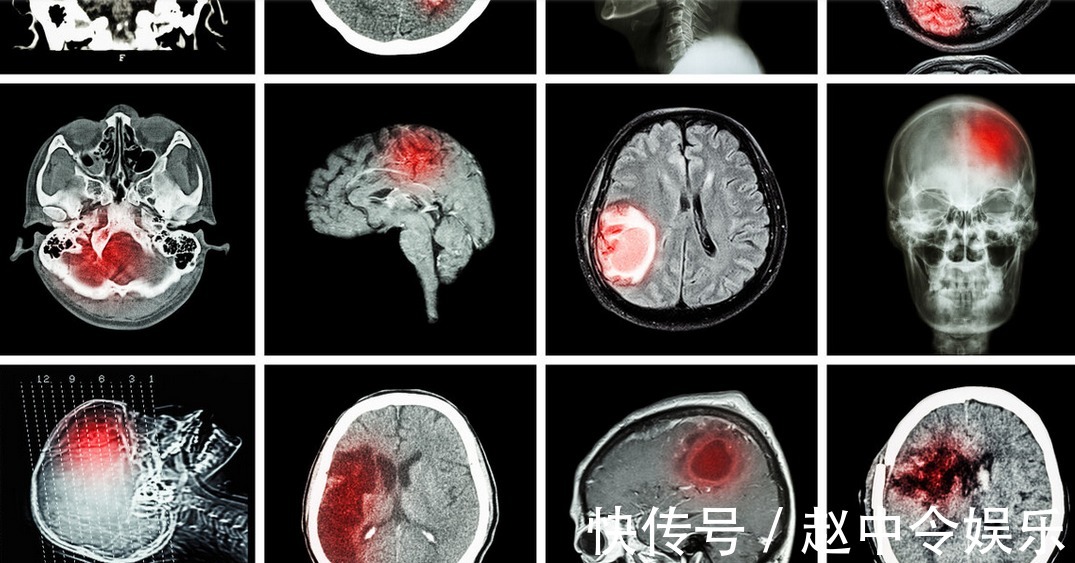

家住辽宁沈阳的郑大哥今年已经54岁了,儿子就在市里国企上班,每周都能回家来看一看,最近儿子开始准备和准备谈了几年的女朋友结婚,这可把郑大哥给乐坏了,出门就向别人炫耀。事发当天,郑大哥刚刚陪儿子和儿媳看完房子,三个人在外面吃完饭回到家,郑大哥准备看会儿电视,结果坐在沙发上没一会儿,突然感觉头晕眼花,脑袋疼的厉害,话还没有说出来,就眼睛一黑,晕了过去。听到动静的儿子从房间走出来,就看到晕倒在沙发上的郑大哥急忙拨打120,把他送去医院,经过检查发现是急性脑梗发作,脑部血管出现了严重的堵塞,要立即做手术。

经过四五个小时的救治,还是没有挽回郑大哥的性命,儿子后悔不已,原来看房子的时候,郑大哥就说自己头晕,但是儿子以为是中暑,没有在意,结果没想到是脑梗。脑梗是什么呢?脑梗就是脑部血管出现了堵塞,造成脑部的神经组织因为长时间的供血供氧不足而出现软化坏死。对于脑梗患者来说,一旦脑梗发作就可能直接威胁到生命安全,就算救治的及时,也可能留下偏瘫,半身不遂的后遗症,而在脑梗发生之前,身体往往都会有异常的现象,这时就需要我们多加注意,尤其是对于中老年人来说,及时检查,减少病情的发展十分重要。